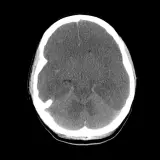

Over 2,100 interactive radiology cases, curated by radiologists for your level of training. Scroll, window, and view cases full screen — just like on PACS. Click linked findings in each writeup to jump straight to them on the image. Cases include sample reports, a focused discussion section, original illustrations, and videos.

完全交互式病例,配备您在 PACS 上期待的各项工具——滚动、调窗、缩放、平移、测量、ROI 和全屏模式。

丰富的标注直接在病例图像上突出关键发现。点击病例讲解中的关联发现,即可跳转至其在扫描上的精确位置。